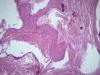

Опухоль матки |

Плоскоклеточный умереннодифференцированный рак,инвазия в железы.